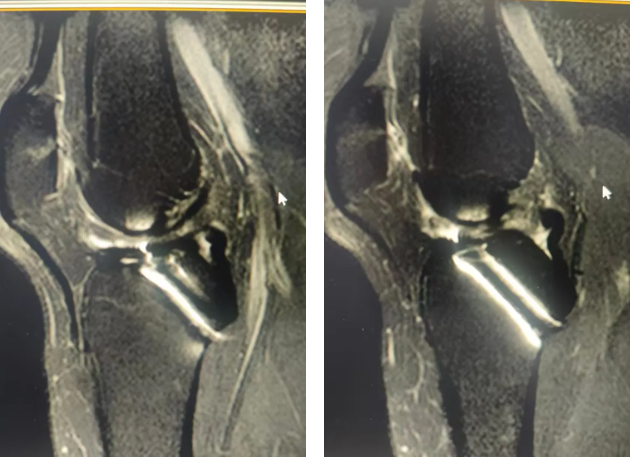

术前膝关节MRI检查

术后复查膝关节MRI检查